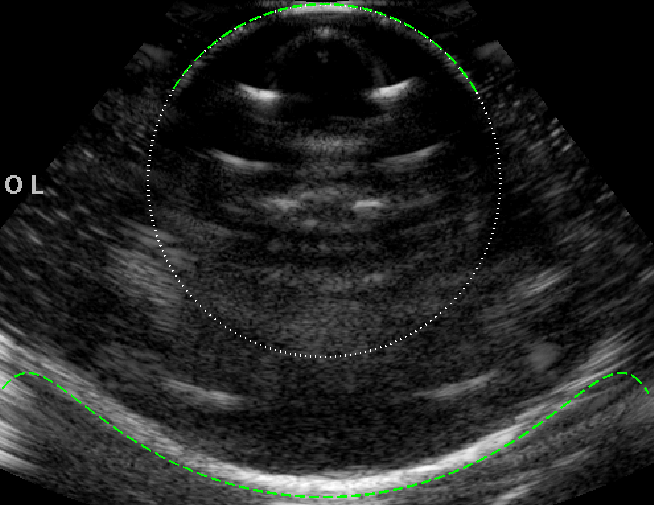

As an initial validation we filled both the object and bath with ethanol-water mixture, such that the system has uniform speed of sound throughout, m s-1. The -mode, shown in figure 2(a), shows a circular image boundary, confirming the absence of geometric distortion, and matches well to the expected circular shape of the object (green dashed line). Note the intensity distortion around the boundary: the poles of the object are brightest as a result of specular reflection.